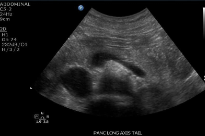

Sag Pancreas whole

transverse position w head neck body

Sag pancreas head

Sag Pancreas neck/body

Sag pancreas neck

Sag Pancreas tail

Trv Pancreas